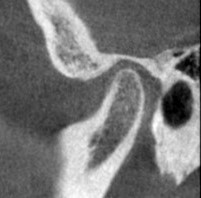

右側の関節のCTスキャンです。

こちらも同じくです。

両側音が鳴るのもうなずけます。